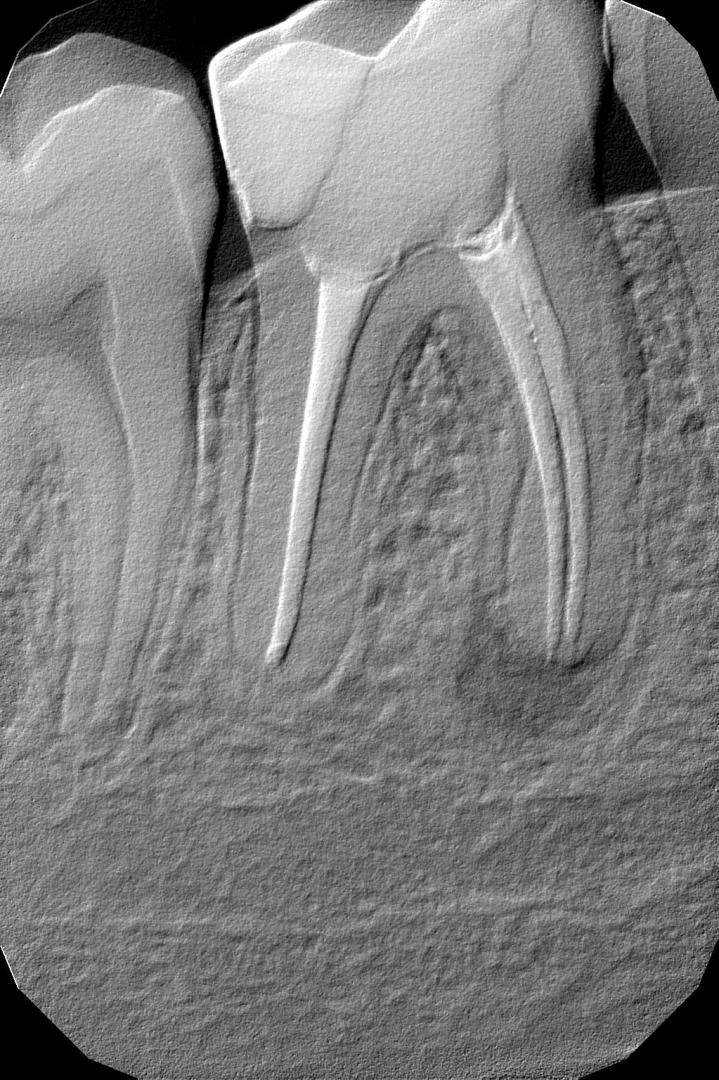

- Точкове зображення зуба